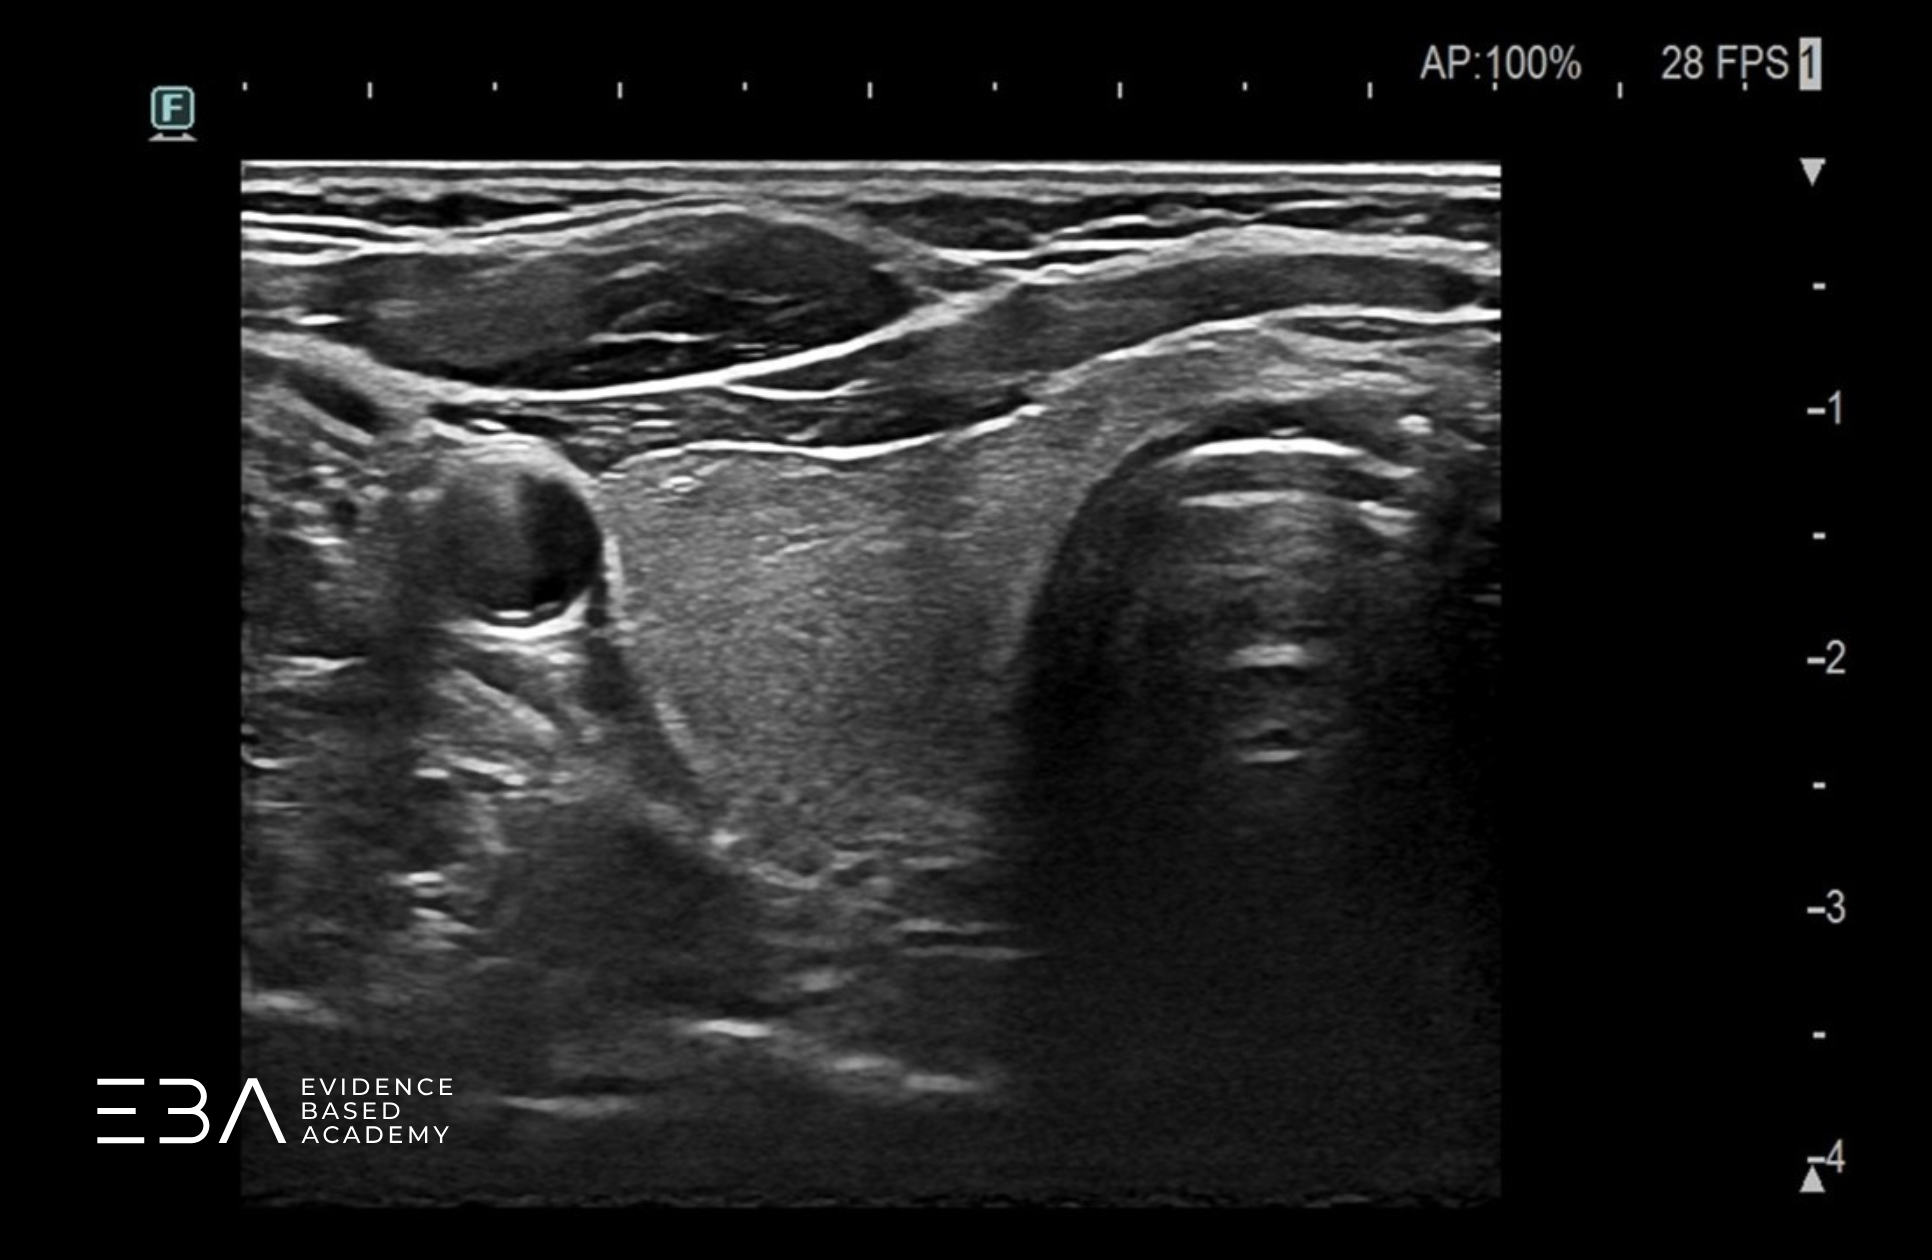

Pomiar w przekroju podłużnym

Uzyskując przekrój podłużny przez płat, wybieramy miejsce, w którym płat jest najdłuższy. Po zatrzymaniu obrazu umieszczamy kursor w najdalej położonym punkcie górnego bieguna i wyznaczamy linię do najdalej położonego punktu bieguna dolnego, zgodnie z osią długą płata.

Pomiar długości płata głowicą liniową.